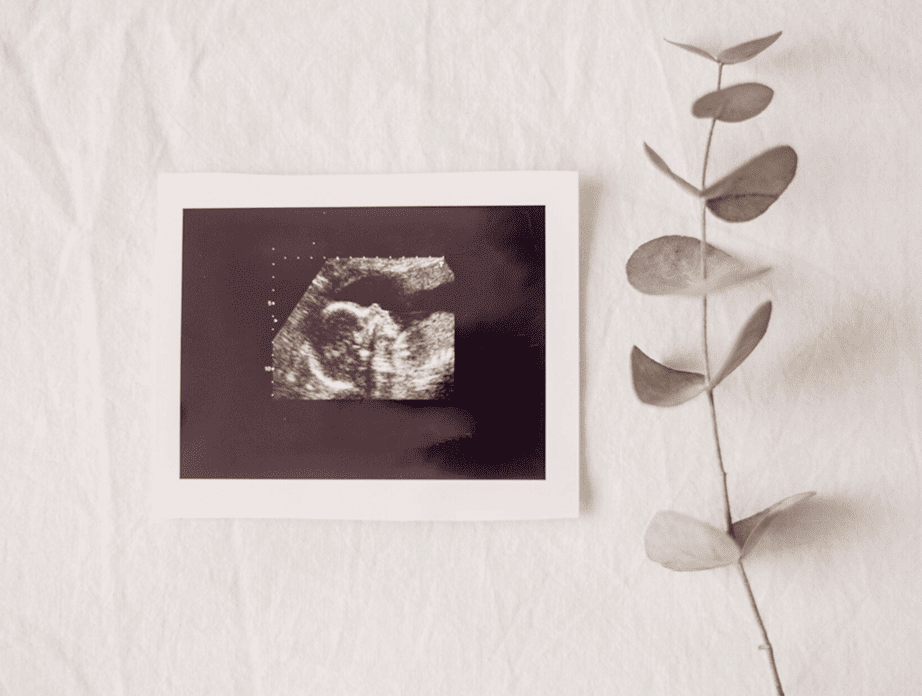

ULTRASONIDO OBSTÉTRICO

Una ventana segura para observar el desarrollo de tu bebé durante cada etapa del embarazo.